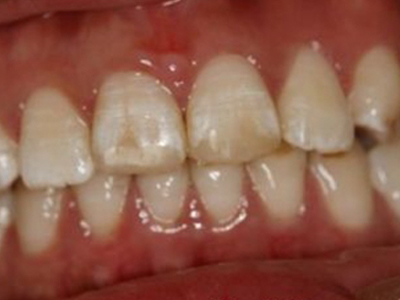

牙釉质发育不全牙齿上有褐色坑图

牙釉质发育不全的患者随着疾病逐渐发展,除了出现牙齿表面发白、不通透外,还可有褐色的条状、窝状凹陷,继之出现数条并列的凹陷。